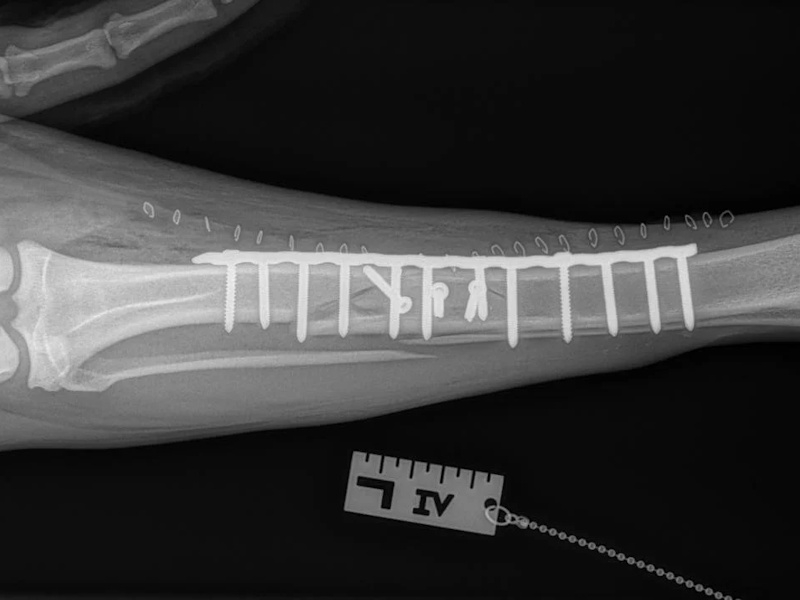

An osteotomy is a surgical cut in a bone. In the cruciate deficient stifle, a cut is made in the top of the tibia. The top portion of bone that contains the articular surface is rotated to level it. The two pieces of bone are held in place with a metal plate and screws.

Post Surgical Radiographs

While the patient is still anesthetized, the patient is taken into radiology for post-surgery radiographs (X-rays). The radiographs are assessed to measure the new tibial plateau angle. We are aiming for 5-6 degrees relative to the long axis of the tibia. The apparatus (plate and screws) are assessed for size and appropriate position.